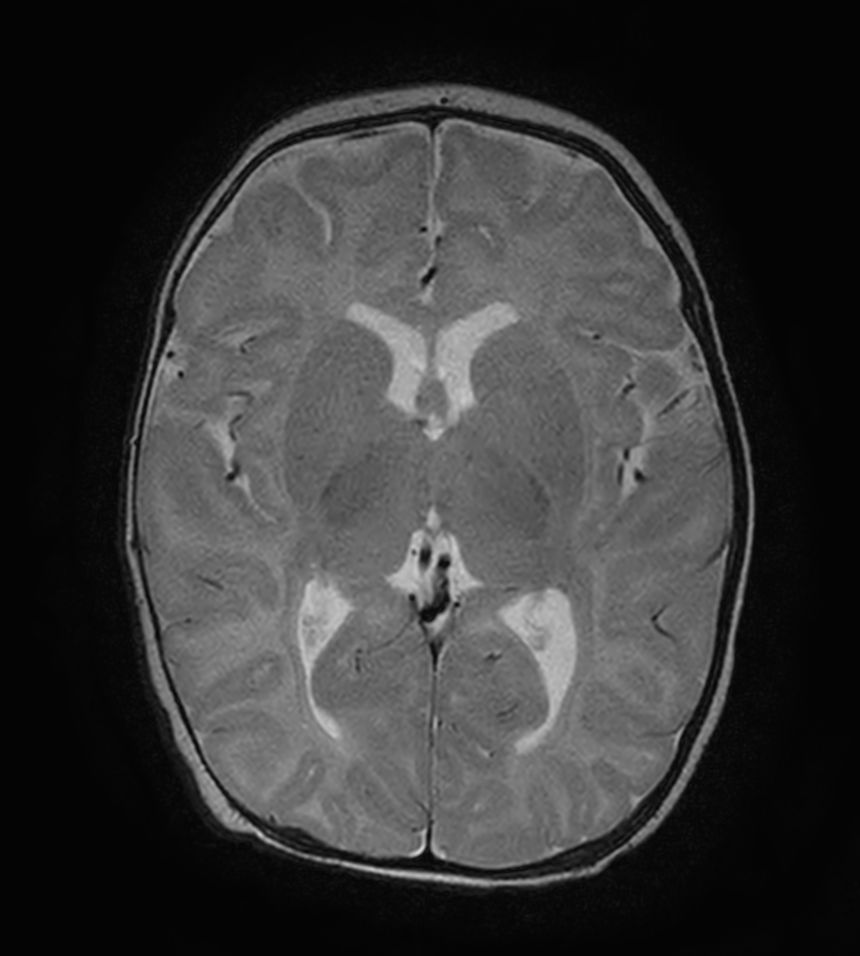

Axial T2w TSE with ComforTone